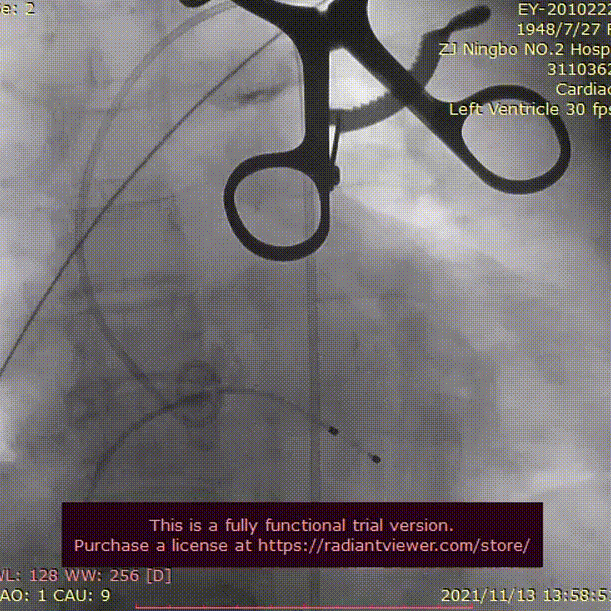

沿导丝送23 mm球囊至主动脉瓣口,定位准确后,在180次/分临时起搏下用球囊扩张狭窄的主动脉瓣,观察造影见大量返流,经过大家讨论后决定退出23mm球囊后再次送入25mm球囊进行预扩,同时观察造影见无返流,冠脉情况良好。后沿导丝送入VenusA-Plus®可回收输送系统L29型号瓣膜缓慢释放,同时确认冠脉情况,植入后经多体位投照和主动脉根部造影,显示瓣膜释放位置满意,瓣膜形态良好。术后未出现并发症,手术取得圆满成功。